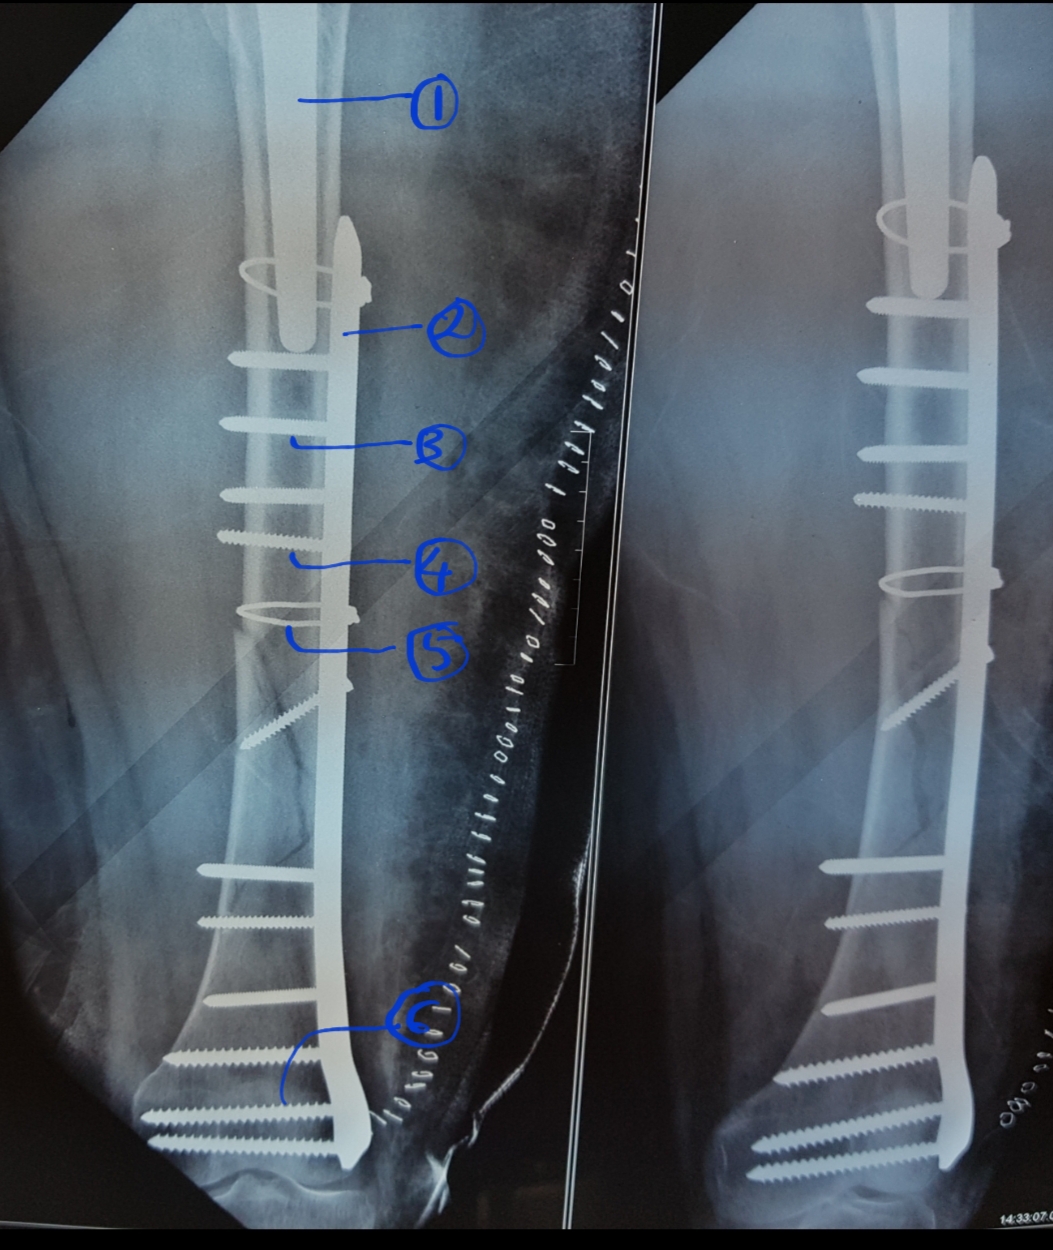

Vancouver classification of peri prosthetic fracture

Used in post operative peri prosthetic femoral fracture following a hip arthroplasty.

Type A: Fracture involving trochanteric region.

Type B:Fracture around stem or immediately distal to it

Type C:Fracture far distal to prosthesis

1.Hip prosthesis

2.Fixation plate

3.Locking screws

4.Cortical screws

5.Circlage with cable

6.Cancellous screws